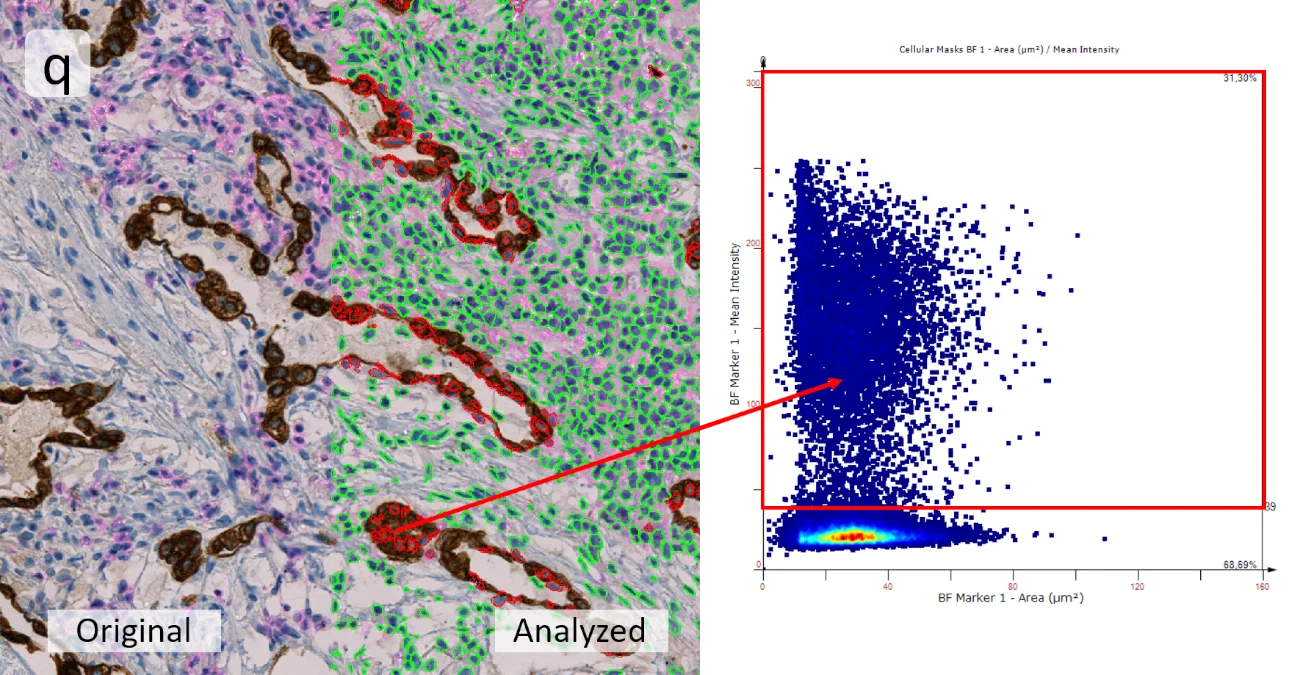

To assess the percentage of marker-positive cells, scattergrams are generated, and a cut-off on marker intensity was set to distinguish between marker+ and marker- cells. To visualize these marker+ cells directly in the image (q), they can be selected by the backward connection feature from the corresponding scattergram (red mask). Additionally, if the scattergram is presented as a heatmap, it will give an indication where most cells are concentrated, which can help to adjust the cut-off.